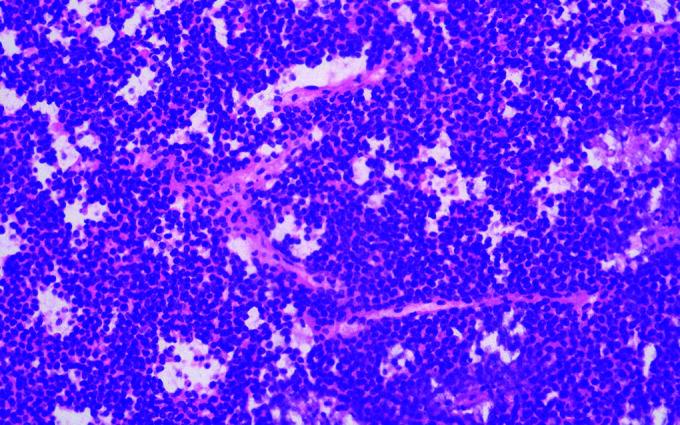

There is a relatively high incidence of patients recalling an injury before the appearance of a musculoskeletal (MSK) mass, especially in the hand and upper limb. Despite numerous reports of such cases, no clear pathogenetic mechanism has been elucidated to explain this. A tumour may be pre-existing, with the injury bringing the patient's attention to it, or develop coincidently following trauma. Alternatively, injury or the resultant reparative mechanisms may initiate or accelerate tumour formation. Following such a case presenting to our unit, a narrative review of the literature was conducted to determine what evidence existed to support or refute these hypotheses. This is presented along with the case. Though trauma as a cause of MSK tumours cannot be excluded, there is a lack of scientific evidence to support this theory, and further research in the field of pathophysiology and molecular biology is necessary. It is important that clinicians caring for trauma patients maintain a high index of suspicion for alternate diagnoses. A local injury may mask tumour development and lead to the incorrect conclusion that persistent symptoms are the result of failure to recover from the injury, rather than having a more sinister explanation.

有相当一部分患者在肌肉骨骼(MSK)肿块出现之前回忆起曾受过伤,尤其是在手和上肢部位。尽管有许多此类病例的报告,但尚未阐明明确的致病机制来解释这一现象。肿瘤可能原本就存在,受伤使患者注意到它,或者在创伤后 coincidently 发生。或者,损伤或由此产生的修复机制可能引发或加速肿瘤形成。在我们科室遇到这样一个病例后,对文献进行了叙述性综述,以确定有哪些证据支持或反驳这些假设。现将其与病例一同呈现。虽然不能排除创伤是MSK肿瘤的病因,但缺乏科学证据支持这一理论,因此在病理生理学和分子生物学领域有必要进行进一步研究。重要的是,治疗创伤患者的临床医生要对其他诊断保持高度怀疑。局部损伤可能掩盖肿瘤的发展,并导致错误的结论,即持续症状是受伤后未能恢复的结果,而不是有更险恶的原因。